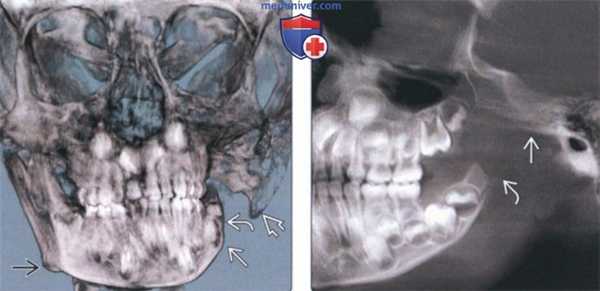

(Слева) На панорамной реформатированной КЛКТ определяется уменьшение мыщелка, обусловленное ревматоидным артритом, и типичное его уплощение («заточенный карандаш»). Такая картина часто наблюдается при ревматоидном артрите.

(Справа) На кадрированной панорамной реформатированной КЛКТ у этого же пациента определяются признаки ревматоидного артрита левого ВНЧС. Двухстороннее поражение - характерный признак ревматоидного артрита. Воспалительный процесс распространяется и на мыщелок, и на суставную ямку. (Слева) На сагиттальной КЛКТ (поперечный срез под углом) у этого же пациента определяется уплощение и деформация передневерхнего края мыщелка с характерным заострением его заднего края.

(Справа) На сагиттальной MPT (Т1ВИ, под углом) у этого же пациента определяется паннус в суставном пространстве с деструкцией суставных поверхностей суставной ямки и мыщелка. (Слева) На сагиттальной КЛКТ правою мыщелка (под углом) определяется деформация поверхностей суставной ямки и мыщелка, часто наблюдающаяся при ревматоидном артрите. Уменьшение высоты и объема мыщелка обусловлено данным воспалительным процессом.

(Справа) На корональной КЛКТ (под углом) у этого же пациента определяется деформация суставных поверхностей уменьшение размеров мыщелка, сужение суставного пространства. Такая картина может быть неотличима от дегенеративного заболевания сустава. (Слева) На панорамной реформатированной КЛКТ нижней челюсти справа у пациента с двухсторонним ювенильным идиопатическим артритом ВНЧС определяется уменьшение мыщелка и укорочение шейки. Задний скат суставною возвышения упло щен и располагается горизонталь но. Видна также глубокая антегониальная вырезка.

(Справа) На панорамной реформатированной КЛКТ у этого же пациента визуализируется короткая левая ветвь. Виден формирующийся в ветви третий моляр. Плоскость нижней челюсти наклонена книзу. (Слева) На панорамной реформатированной КЛКТ у пациента с гемифациальной микросомией определяется задняя инклинация маленького деформированного мыщелка. Обратите внимание на уменьшение высоты тела нижней челюсти, укорочение ветви, отсутствие суставного возвышения.

(Справа) На сагиттальной MPT (Т1 ВИ) у пациента с остеохондромой левого ВНЧС визуализируется мягкотканная опухоль, разрушающая мыщелок и заполняющая мыщелковую ямку. Типичные кольцевидные кальцинаты в этом случае не визуализируются. (Слева) На панорамной рентгенограмме определяются метастазы рака молочной железы в нижней челюсти. Правый мыщелок выглядит маленьким, склерозированным и «пятнистым» за счет участков деструкции. Верхние отделы ветви склерозированы, кортикальные пластинки отсутствуют, задний край деформирован.